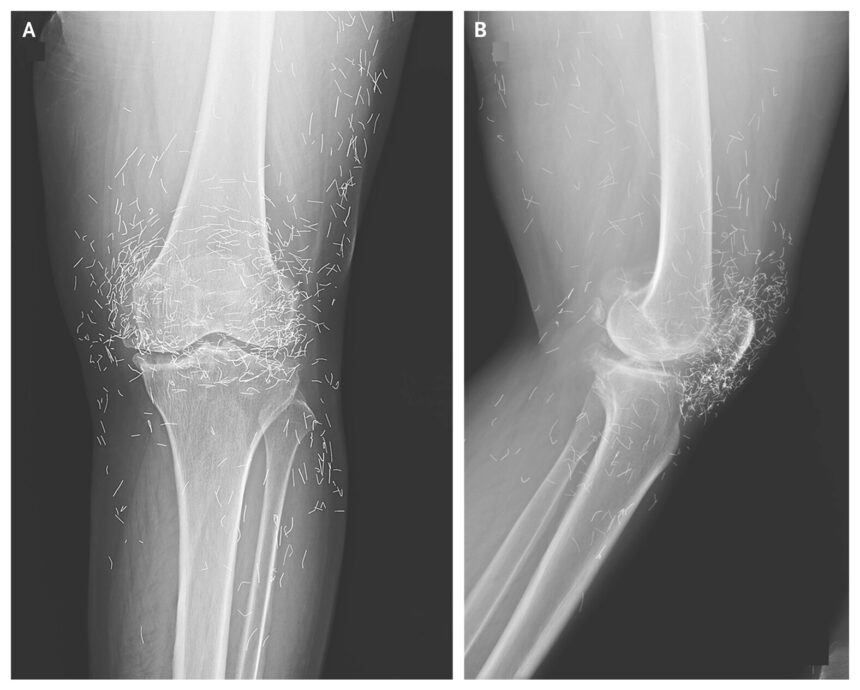

Uma mulher de 65 anos buscou atendimento relatando dores fortes nos joelhos depois de um diagnóstico de osteoartrite. O médico pediu um raio-X para avaliar a região e levou um susto com a imagem: havia vários pontos brilhantes no tecido ao redor da articulação. Segundo o especialista, eram “fios de ouro” deixados por um tratamento alternativo ao qual ela havia recorrido (veja a imagem acima).

O caso foi relatado no jornal New England Journal of Medicine, em que os autores fazem um alerta sobre a busca por terapias sem evidência científica — prática que pode piorar quadros como o da osteoartrite e atrasar tratamentos eficazes.

➡️ Como isso é feito? Durante a terapia, pequenas partículas — ditas de ouro — são colocadas na ponta da agulha e acabam sendo inseridas no corpo. Há dezenas de posts em redes sociais oferecendo esse tipo de serviço como “tratamento para dor”.

➡️ Essas partículas não conseguem ser absorvidas pelo corpo e acabaram ficando acumuladas na região já doente e ampliando a dor.